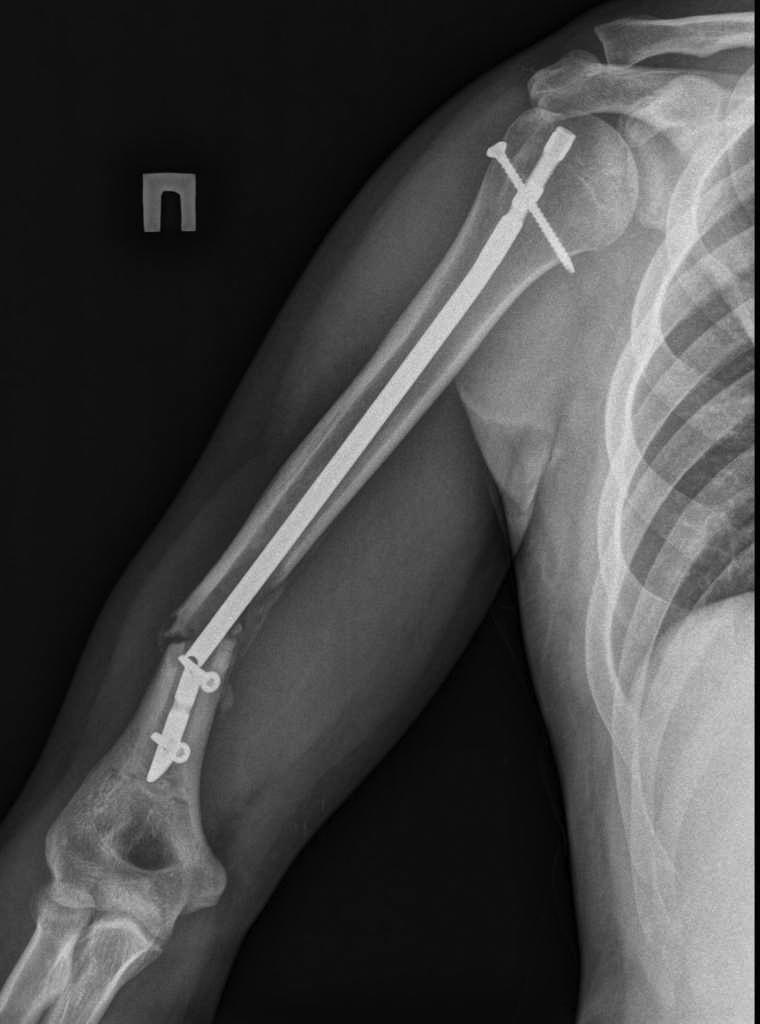

Здравствуйте уважаемые форумчане. Представляю Вашему вниманию очередной сломанный

штифт. Пациент 25 лет, в сентябре 2012 г ДТП. Кроме всего прочего, открытый перелом правого

плеча с дефектом костной ткани. При поступлении выполнено ПХО и ЧКО из 2 колец. После

заживления раны выполнен БИОС плеча. Штифт сОлидный, Остеомед. Пару дней назад во время

попытки открытия крышки банки (нагрузка по ротации) почувствовал боль в плече. Результат на

снимке. Планируем удалить оба отломка (дистальный открыто) и перештифтовать более

массивным штифтом. Вопрос 1: есть ли вариант в данном случае закрыто удалить дистальный

франгмент НЕканюлированного штифта. Особых инструментов для удаления сломаных штифтов не

имеем. Вопрос 2: как вариант рассматриваем выполнить ЧКО удалив предварительно только

проксимальный фрагмент штифта. СтОит ли? Вариант накостного остеосинтеза с пластикой и без

не рассматриваем. Спасибо за внимание.